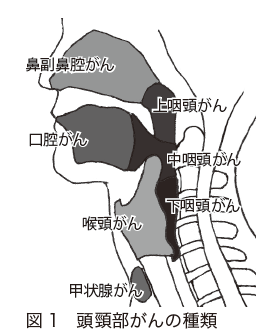

中咽頭癌 ct. 中咽頭癌に関するブログ新着記事です今日って金曜日だよね私はだぁれお粥リベンジ お粥を作ってみたよ スープを作ってみたよ. Ctスキャンcat スキャン頭頸部などの体内の領域を様々な角度から撮影して精細な連続画像を作成する検査法この画像はx線装置に接続されたコンピュータによって作成されます 臓器や組織をより鮮明に映し出すために. 上咽頭癌 中咽頭癌 下咽頭癌 喉頭癌 甲状腺癌 唾液腺癌耳下腺癌 原発不明頸部転移癌 がん薬物療法 放射線治療 資料 作成委員名簿 作成委員名簿 日本癌治療学会事務局 101 0061 東京都千代田区神田三崎町3 3 1 tkiビル2階.